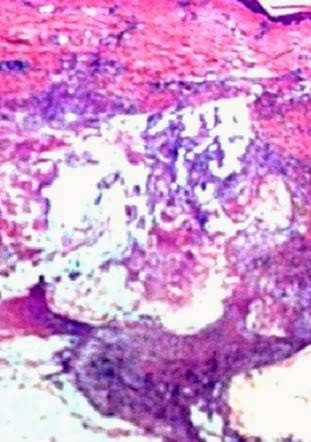

Dermatopathology Case 124 Get link Facebook X Pinterest Email Other Apps January 29, 2014 Image1 (Low power) Image2 (Low power) Image3 (High power) Image4 (High power) Case 124: A 45 year old man with painful reddish brown nodule on the left thigh. Patient also has a history of acute pancreatitis. Spot Diagnosis: Get link Facebook X Pinterest Email Other Apps